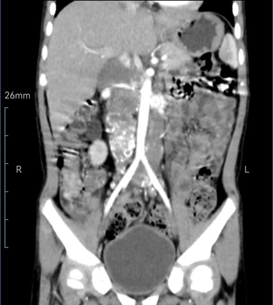

经过检查和诊断,医生发现小喜腹腔里的肿瘤不仅非常大,而且有骨髓转移的迹象,肿瘤包绕着腹主动脉、下腔静脉、肾动静脉等多条重要血管,小喜处于神经母细胞瘤Ⅳ期,失去了手术机会。

随后小喜顺利接受了四个疗程的化疗,庆幸的是,小喜的化疗效果非常好,不仅能耐受化疗的副作用,而且 4 月的腹部 CT 复查结果显示肿瘤明显缩小,这场与死神的较量终现曙光。

为了确保这场较量的胜利,手术前,市妇幼保健院小儿外科副主任 安俊军、副主任医师 冯运红 医生团队,多次展开病历讨论。医生团队借助医院先进的 3D 重建及打印技术,对小喜的肿瘤与周围重要血管的关系进行建模,明确了肿瘤的边界、包绕血管、淋巴结转移等情况,从而更直观地规划手术方案,尽最大程度避免术中意外的发生。

4 月 15 日,小喜被推进了手术室。随着手术的进行,肿瘤赫然入目,医生发现情况与术前分析预估的一致:肿瘤位于脊柱体右缘,下腔静脉被推挤并部分包绕,腹主动脉及其发出的肾动脉血管深不可见…… 经过 7 个多小时的努力,医生终于顺利地将小喜体内的肿瘤完全摘除,同时清扫了腹主动脉旁转移的淋巴结。